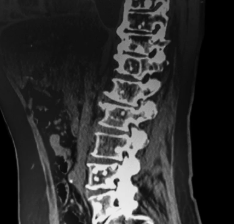

MRI or ultrasound performed by our orthopedic specialist.